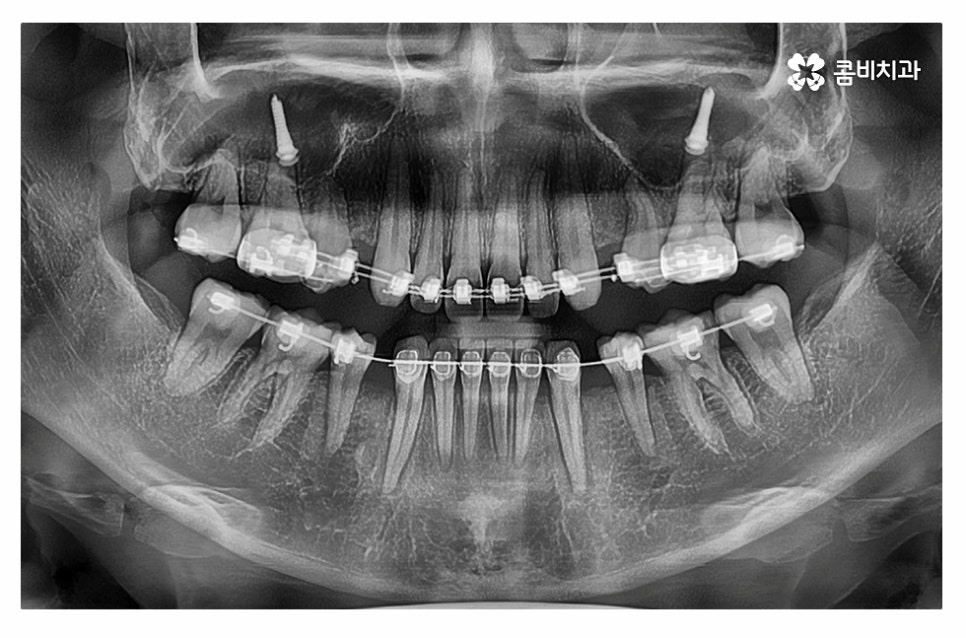

위 환자분의 경우 정면에서 보이는 치열은 가지런한 편이지만

치아가 돌출되어 돌출입으로 고민했던 사례이며

치아의 이동 공간 확보를 위해 발치 교정을 진행한 사례라고 할 수 있어요.

윗니는 설측교정으로 진행하고 아랫니는 일반적인 순측교정으로

치료를 진행하는 방식을 콤비교정이라고 부르고 있는데요.

돌출입치아교정은 돌출입의 원인을 정확하게 파악하는 것이 중요한데

일반적으로는 발치를 하는 경우가 많지만 구강구조 및 골격 등은

개인에 따라 다르기 때문에 치간 삭제, 구개확장 장치 등을 활용하여

비발치로도 치아의 이동 공간을 확보하여 비발치치아교정을 하는 사례도 있어요.